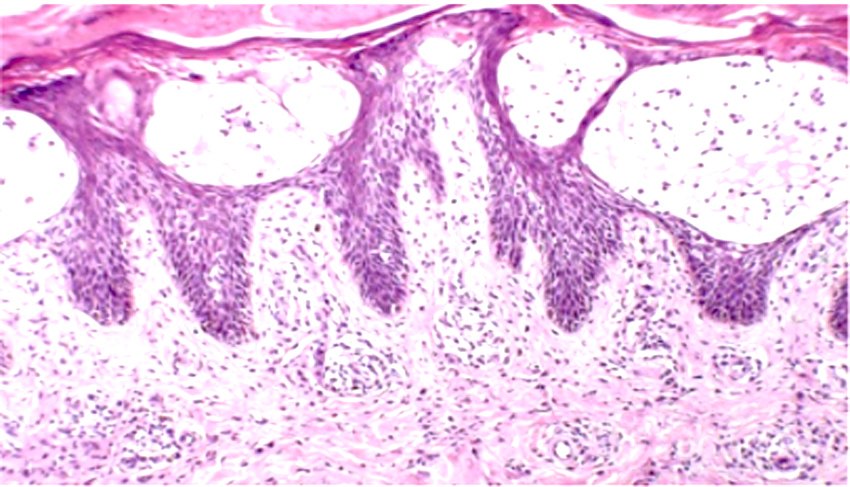

Bazal hücreli karsinom insanda en sık görülen kanserdir. Bazal hücreli karsinom yavaş büyür ve çok nadiren metastaz yapar. SCC gibi immünsüpreselerde ve DNA tamir bozukluklarında sık görülür. Hedgehog yolağındaki PTCH1 geninde bozukluk vardır. Gorlin sendromunda familyal olarak çok sayıda BCC görülür. Histolojik olarak bazal hücreler periferde palizadik dizilime sahiptir. Tümör adaları çevre stromadan çekilmeler gösterir (trikoepitelyoma ile ayrımda önemli) klinikte inci benzeri papüller ve telenjiektatik görünüm vardır.. Pigmente formları malign melanomla karışır.. Rodent ülser tipiktir. Güneşe maruz kalan yerlerde daha sıktır. Squamöz hücreli karsinomun aksine HPV ile ilişkili değildir. Bazal hücreli nevüs sendromunda herediter bazal hücreli karsinom, erken yaşta ve çok sayıda ortaya çıkar. Kemik anomalileri, sinir, göz ve üreme sisteminde anomaliler vardır. (Cevap D)